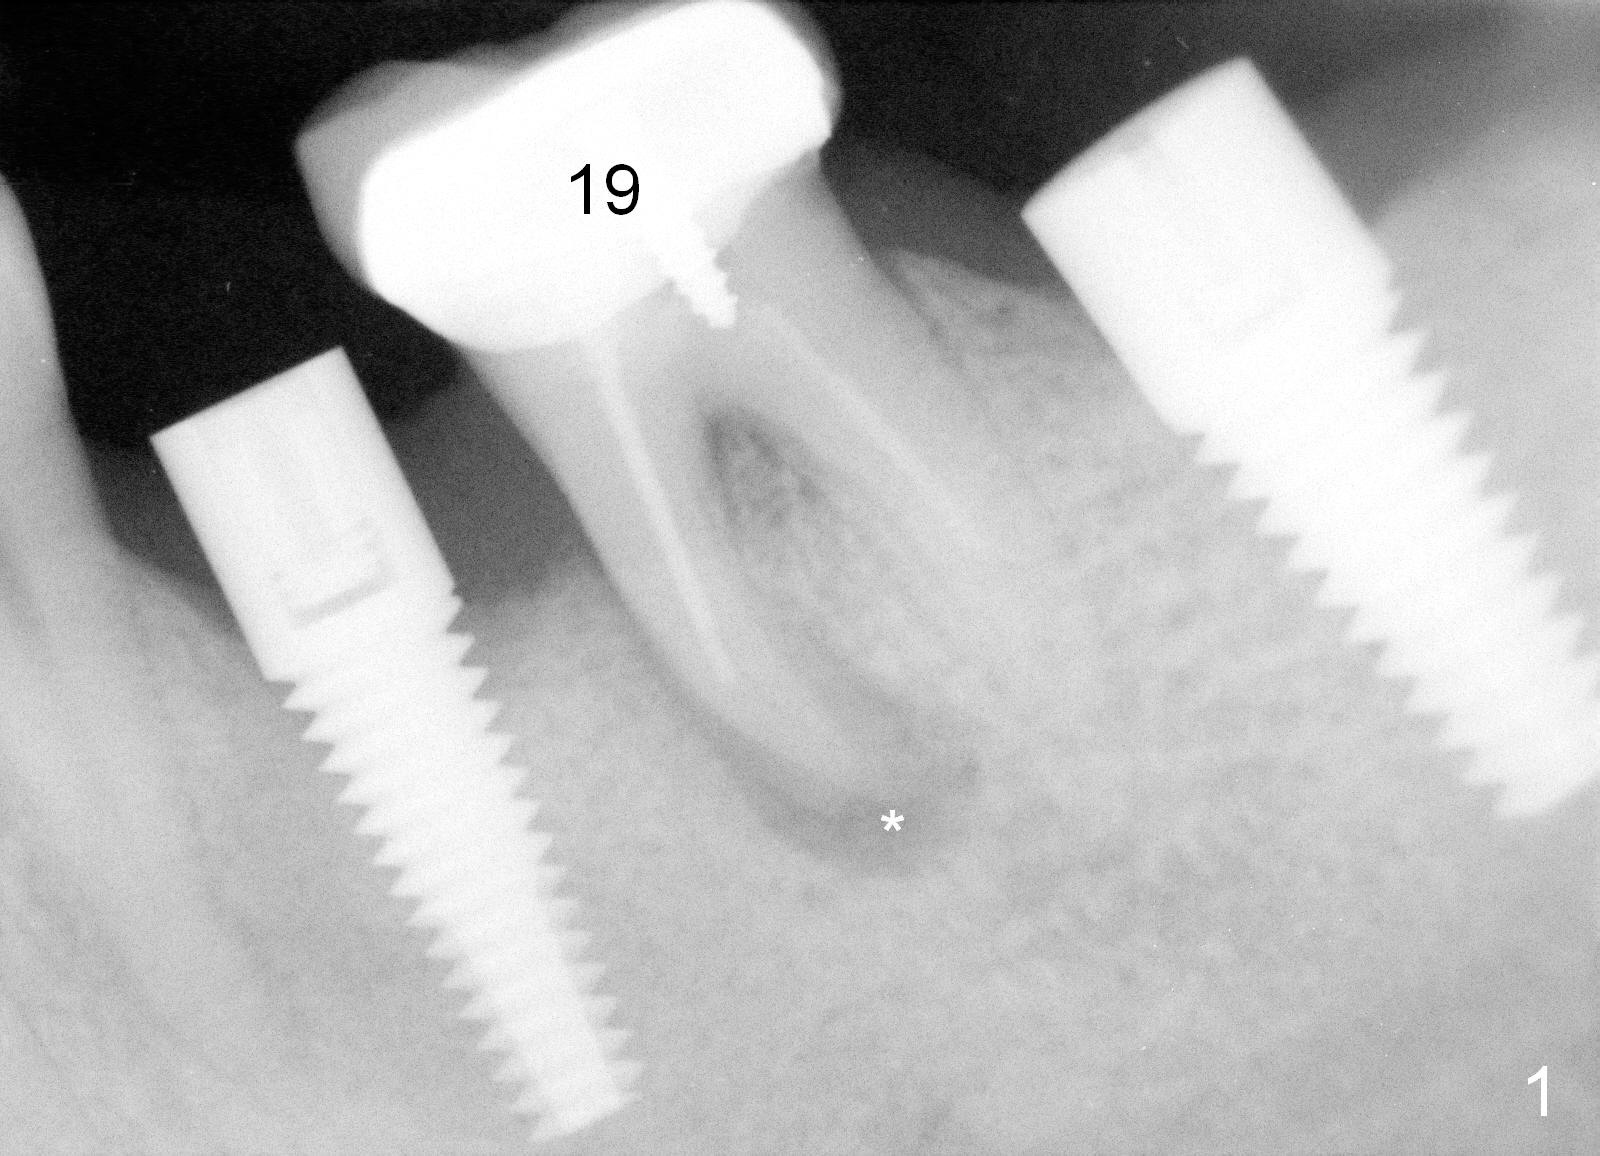

When the infection at the site of #20 is under control, the tooth #19 causes severe pain with mesial periapical radiolucency (Fig.1 *).  Vertical mesial root fracture is confirmed at extraction.  Osteotomy is initiated in the septum (Fig.2 S), but the apical end of the 2 mm pilot drill deviates to the mesial socket.  A Lindamann bur is used to move osteotomy distal, but the implant (6x17 mm) is mainly placed in the mesial socket (Fig.3).  An intraop drawback associated with the deviation is pain control.  The nervous patient questions several times whether it is a good idea to place an implant in the infected site.  Block anesthesia has to be administered.  In fact lack of pain control may be also related to proximity to the Mental Loop (Fig.3 red dashed line).  Fortunately no paresthesia occurs postop, since the implant is somehow placed lingually.